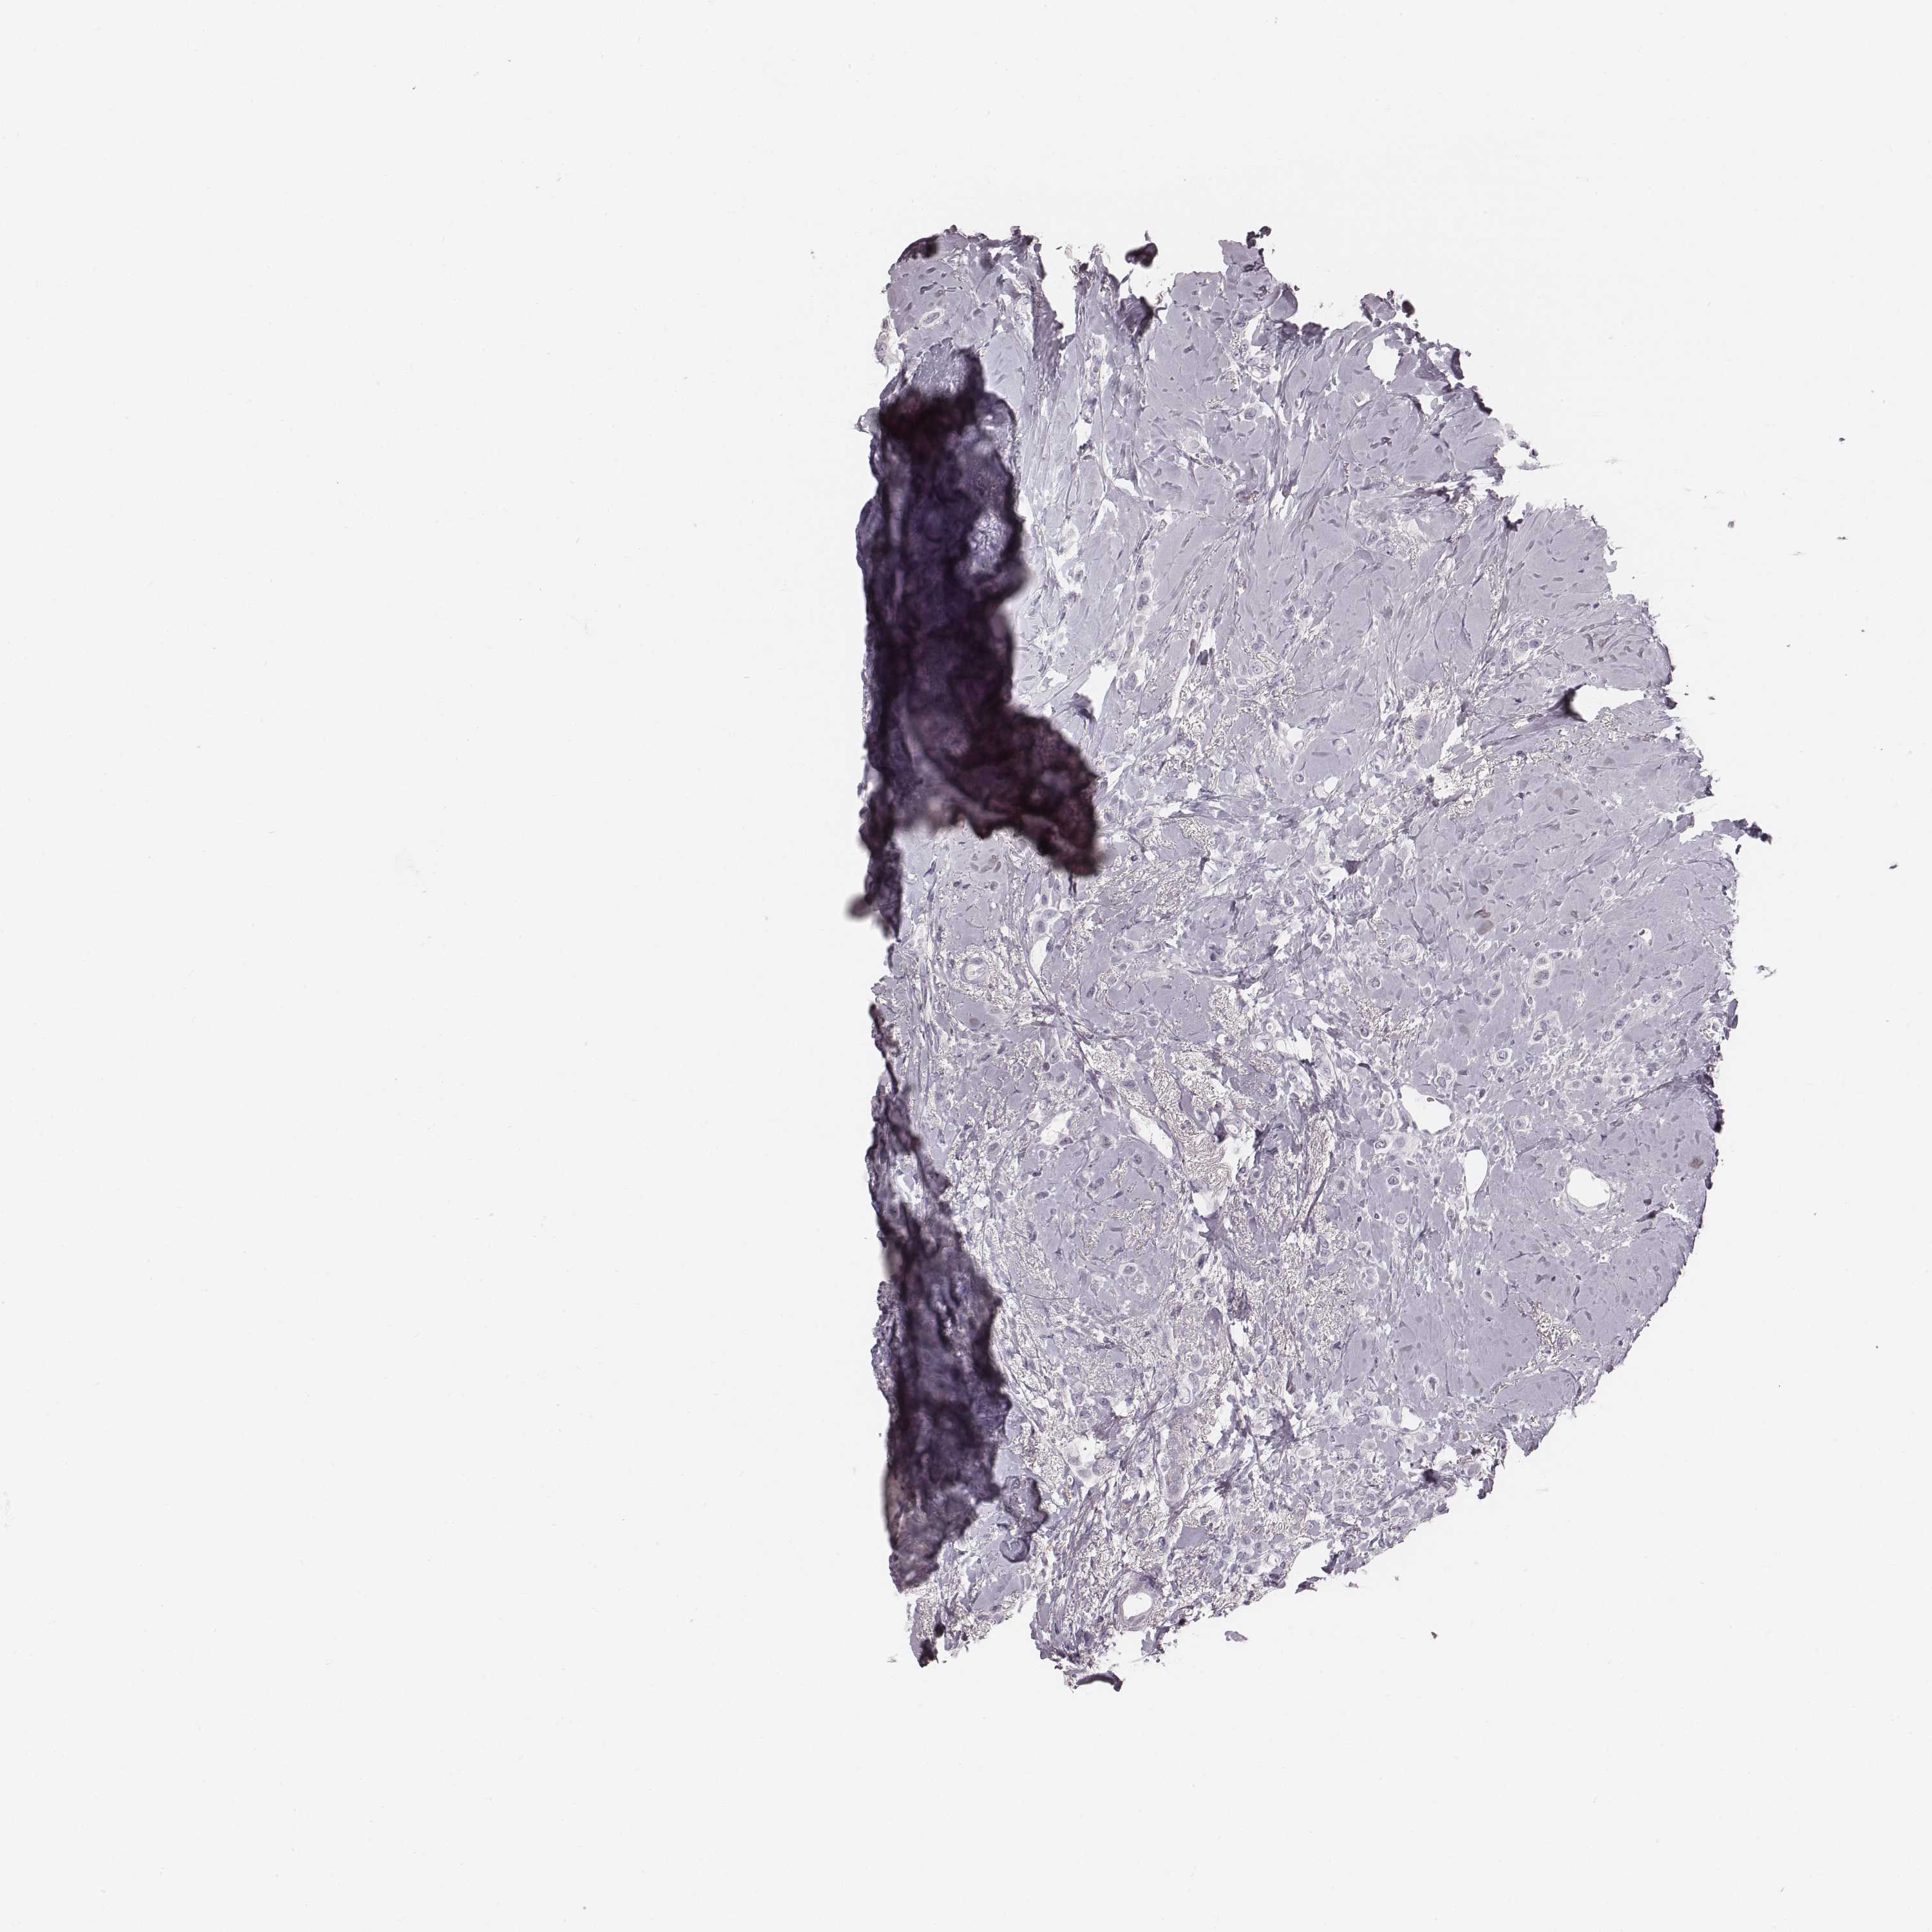

BRCA TCGA BRCA VALIDATION PROTEIN EXPRESSION

ANTIBODIES

AND

VALIDATION